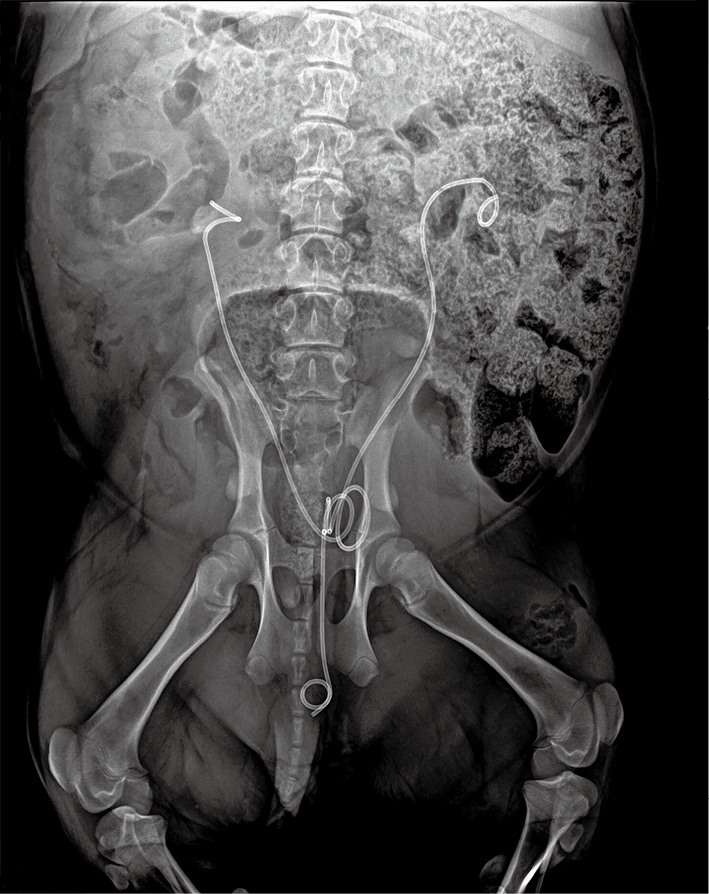

中心致力于提供生物材料与医疗器械临床前有效性评价用动物生物资源的收集、创制、保藏与共享服务,支撑院重大战略与重点任务的实施。2024年度中心构建了多种疾病模型,并服务于各研究所、高校和医院,包括脑电极植入动物模型、复合感染性疾病动物模型、心血管疾病动物模型、骨相关疾病动物模型、泌尿系统疾病动物模型、皮肤相关疾病动物模型、眼科疾病动物模型、肿瘤疾病动物模型和口腔相关疾病动物模型等。

1)初步建立了脑机接口评价平台,购置脑立体定位仪、神经电生理信号分析仪等仪器设备搭建硬件基础条件;与首都医科大学附属北京天坛医院神经外科开展合作,提升脑神经电极植入动物模型构建与神经电信号分析能力;积极参与培训与学术会议,紧跟研究前沿并开展相关研究与服务。全年开展小鼠电极脑植入模型30余批次,支撑多项科研项目的实施。

2)平台立足自身科研方向成功完成抗菌导尿管的科研转化,完成产品的动物有效性评价与临床试验,通过了国家药品监督管理局医疗器械技术评审中心组织的专家评审,即将取得三类医疗器械注册证;顺利开展了多批次抗菌防垢输尿管支架的动物有效性评价工作,分别进行了兔输尿管原位植入和猪膀胱植入试验,其相较于对照品与进口市售产品显示出更加优异的抗菌防垢效果。

图3-42 输尿管植入模型